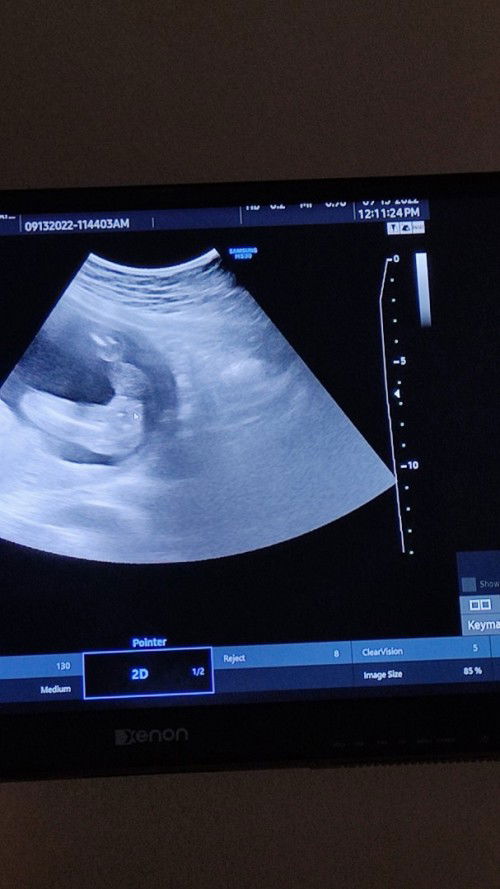

Baby girl ba talaga?..

Mga Mi..tanong lng.. baby girl bah talaga? sabi kasi ni OB baby girl. Saktong 20weeks ako pag utz sa gender nya. Kaso pahalang ang position ni baby nyan.. Nakita yan sa left side ng tummy ko..sabi din ng iba baby boy kasi daw dami ko pimples ngayon at medyo lumapad ilong ko. Haha.. 😅

I think girl kasi wala pong lawit at hindi naman porket ma pimples eh boy na, Wala pong basehan yun